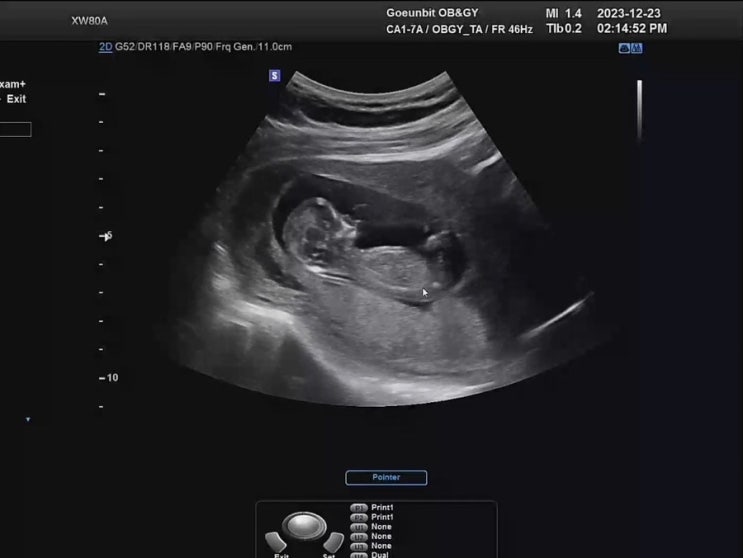

임신 13주차 기록 - 장꾸맘의 각도법, 각도법 성별 보는 법

안녕하세요 보리입니다. 새해가 코앞으로 다가왔네요 2024년은 다른해보다 특별한 해! 바로 보리를 만나는 ...